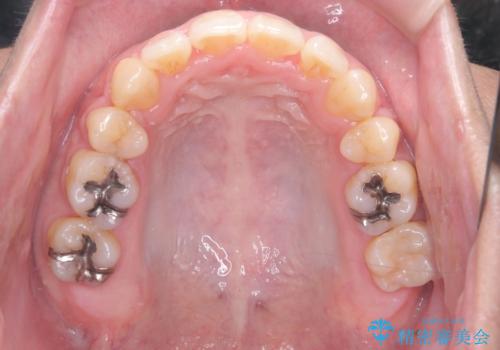

正面から見たときに右上2が全く見えないくらい、右上2が後ろに引っ込んでいる状態でしたが綺麗に並べる事が出来ました。

笑った時のスマイルラインもかなり綺麗になり大変ご満足いただく事が出来ました。

スムーズに治療を進める事ができ、2年2か月で治療をお終えました。

顔貌に対して歯の正中も合いました。